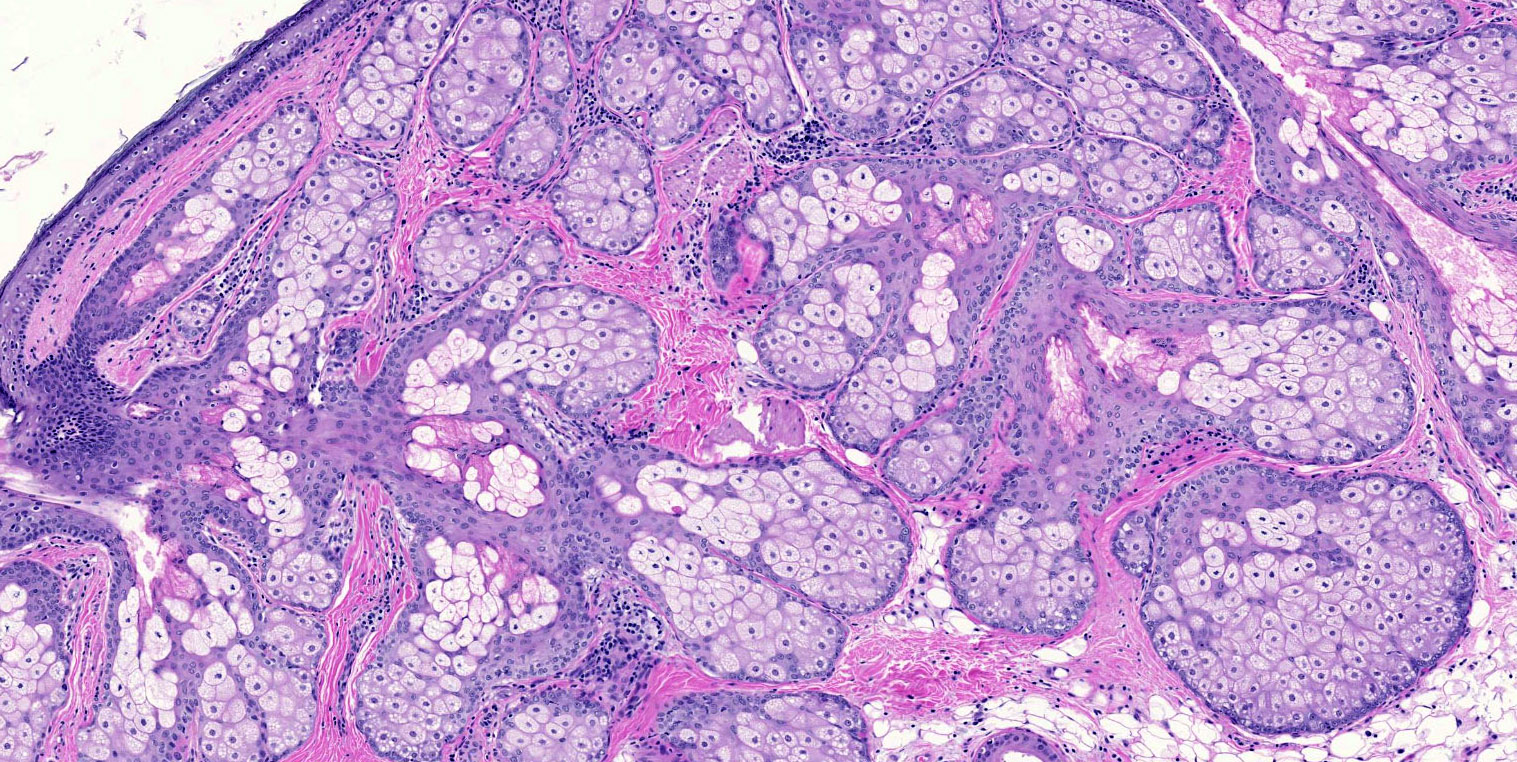

Microscopic (histologic) description

- Mixture of mature, benign tissues

- Ectodermal (most common): squamous epithelium, sebaceous glands, hair follicles, brain tissue

- Mesodermal (second most common): bone, cartilage, smooth muscle, fibroadipose tissue

- Endodermal: intestinal or respiratory epithelium, thyroid, salivary gland

- Microscopic foci of immature neuroepithelium (less than or equal to 4 foci or 21 mm2) does not warrant diagnosis of immature teratoma and will not affect prognosis (Int J Gynecol Pathol 1987;6:203)

- Fat necrosis and foreign body reaction may be seen

- Cases associated with NMDAR encephalitis usually show neuroglial tissue associated with lymphoid aggregates with germinal centers, low number of mature neurons and a hypercellular astrocyte population (Am J Surg Pathol 2019;43:949)

- Reference: StatPearls: Cystic Teratoma [Accessed 29 July 2021]

Microscopic (histologic) images